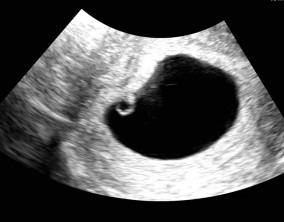

임신 수치 16, 9주차 기적의 기록